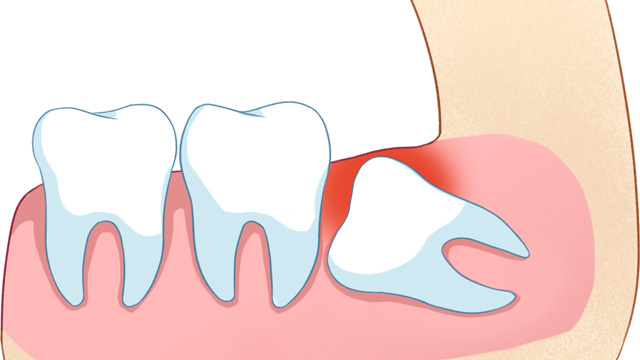

这是最常见的拔除原因。正畸的核心需求之一一般是“排齐拥挤牙齿”,而智齿作为口腔中最后萌出的牙齿(通常在20岁左右萌出),由于生长位置特殊、空间有限,很可能会持续挤压旁边的第二磨牙,导致第二磨牙倾斜、移位,进而引发整个牙列拥挤。

如果不拔除这颗“肇事智齿”,即使通过正畸排齐了牙齿,后期也会因为智齿的持续挤压,导致牙齿再次拥挤、反弹。

02智齿阻挡正畸牙齿移动

正畸治疗中,医生会根据诊疗方案,让牙齿沿着预设轨迹移动(比如前牙内收、后牙调整咬合等)。比如需要内收前牙改善凸嘴时,智齿的存在会“顶住”后牙,导致牙齿无法顺利移动到理想位置。这种情况,可能需要拔除智齿来为排齐牙齿提供必要的空间。